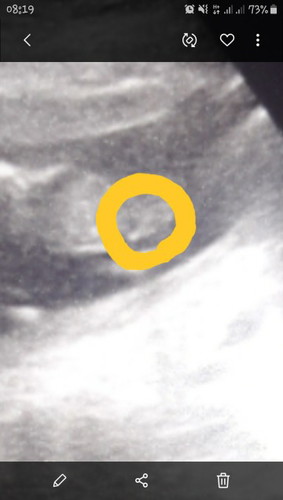

แม่ๆช่วยดูหน่อยค่ะ หญิงหรือชาย

แม่ๆช่วยดูหน่อยค่ะ หญิงหรือชาย ขอบคุณค่ะ

น่าจะชายค่ะ

ไม่เห็นค่ะ